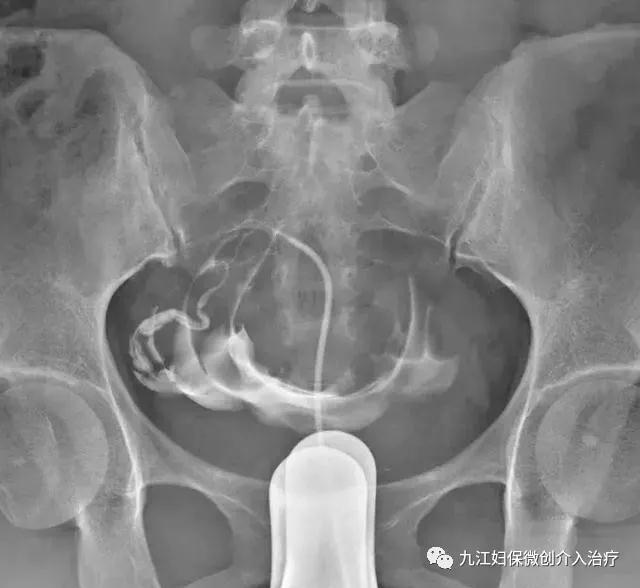

常规消毒铺巾后,充分暴露手术视野。首先进行常规造影确定宫角位置及堵塞部位及程度,再将疏通导管分别选择性超选至堵塞侧子宫角输卵管开口处(间质部阻塞可先用导丝进行机械性分解粘连后引导插管),推注对比剂确认插管至输卵管。

选择性超选插管

经疏通导管缓慢弹性加压向输卵管内推注强效杀菌作用的臭氧气体进行灌注疏通治疗。通过臭氧气体对管腔内的冲洗,使黏液栓子崩解、膜状粘连分离并将黏液栓冲入腹腔。当推注臭氧有明显落空感时即为输卵管通畅。(由于输卵管管腔内形态结构复杂,只有通过灌注气体介质才能对输卵管粘连局部所产生较大的压强,对输卵管粘连产生的分离作用较强,使恢复通畅的机会和程度远较其它方法显示出独特的优越性。)臭氧气体通过输卵管进入盆腔内亦对盆腔粘连起到松解治疗作用,并直接改善了输卵管及盆腔内的无氧环境,抑制厌氧菌的生长。进而可以对输卵管周围的黏连起到一定的治疗作用。

灌注臭氧疏通治疗